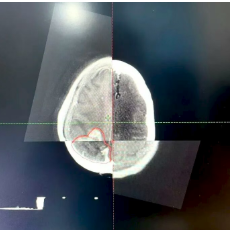

VitalBeam直线加速器落户达州市第三人民医院啦!现已正式投入使用。这个机器可大有来头,它就是在放疗界被誉为“放疗超人”的美国高端进口直线加速器,全市仅此一台。 三院肿瘤科开展放疗工作已有7年,年均放疗约6800人次,科室配套设施设备完善,放疗团队专业可靠,放疗技术成熟。VitalBeam直线加速器的引入使用,将填补我市精准放疗领域的空白,为三院放疗技术达到先进水平提供坚实保障,更为广大肿瘤患者带来新希望。 什么是放疗? 通俗来讲,放疗就是利用直线加速器产生的高能X射线,聚焦照射到肿瘤所在部位,从而杀灭肿瘤细胞。 据世界卫生组织(WHO)统计,目前约70%的恶性肿瘤病人需要在不同时期接受放疗。肿瘤患者中有45%是可以治愈的,其中放疗占18%,手术治疗占22%,化疗等其他治疗方式占5%。 VitalBeam直线加速器的四大优势  1、更快速 剂量率较以往的600MU/min大幅提升,最大可达到1400MU/min,对应的治疗时间从以往的15分钟以上缩短至平均3分钟左右。同时,治疗系统还通过“智能”自动化操作,进一步加快了治疗速度,缩短了治疗时间。这不仅让一些之前无法进行治疗的患者有了治疗机会,还能减少因治疗时间过长而带来的系统性误差和风险。  2、更安全 一方面来自于它的准确性,另一方面它在治疗区域之外的剂量跌落非常快,从而能有效地保护正常的组织和器官,此外,它还具备智能化的自动提示功能,可避免一些不必要的操作。  3、更精准 精度为0.5mm,相比于以往的1mm,精度提高了一倍。其次,它有一整套影像系统,能进行图像引导下(IGRT)的精准治疗,即使肿瘤在治疗期间因患者的呼吸而不断移动,系统依然可以准确捕捉肿瘤的位置。  4、更多功能 功能全面,可开展体部立体定向放射治疗(SBRT)、放射外科治疗(SRS)、图像引导放射治疗(IGRT)、呼吸门控治疗等多种先进治疗技术。 实际案例 使用VitalBeam直线加速器对一例脑胶质瘤患者放疗的步骤 放疗靶区勾画 采用MR和CT图像融合的方式,可准确区分病灶边界。 放疗计划设计 使用非共面旋转容积调强先进技术(VMAT)。 计划评估 处方剂量完全覆盖靶区(红色区域),靶区外正常组织剂量迅速跌落(正常组织受量更低)。 放疗实施 放疗时使用加速器自带锥形束CT进行图像引导(IGRT),自动对准靶区中心,实现了放疗可视化,放疗更加精准。   严格质控,保障质量 三院配备了先进的质控设备:晨检仪、二位矩阵和三维验证系统,定期进行加速器质检和放疗计划验证,确保加速器精度和放疗质量。 VitalBeam直线加速器主要适用于以下疾病 ●头颈部肿瘤:鼻咽癌、口腔癌、口咽癌、颈部肿瘤等; ●胸部肿瘤:肺癌、食管癌、乳腺癌、淋巴瘤及胸腺瘤等; ●腹部肿瘤:贲门癌、胃癌、肝癌、胰腺癌、结直肠癌等; ●泌尿生殖系统肿瘤:宫颈癌、卵巢癌、肾癌、生殖细胞肿瘤等; ● 四肢软组织肿瘤及各部位骨转移瘤; ●部分良性病变:垂体瘤、甲状腺眼凸等。 VitalBeam直线加速器的到来,无疑为三院肿瘤治疗注入了强大动力,我们将以更先进的技术、更专业的团队,为患者提供更优质的医疗服务,守护每一位患者的健康。